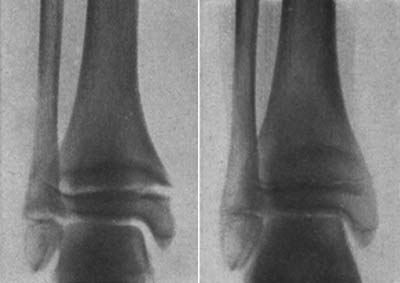

図6.12歳女児.くる病.(左)骨端透亮帯の開大,不明瞭化,杯状変形が認められる.(右)リン酸治療7ヵ月後[19].

全身性骨疾患のX線所見についても初期に多く報告されている.例えばくる病/骨軟化症については,その病理学的な所見はX線発見以前から知られていたが,1920年にはLooser zoneに名前の残る Looserが現在も教科書に記載されている基本的な所見を詳しく報告している[19](図6).